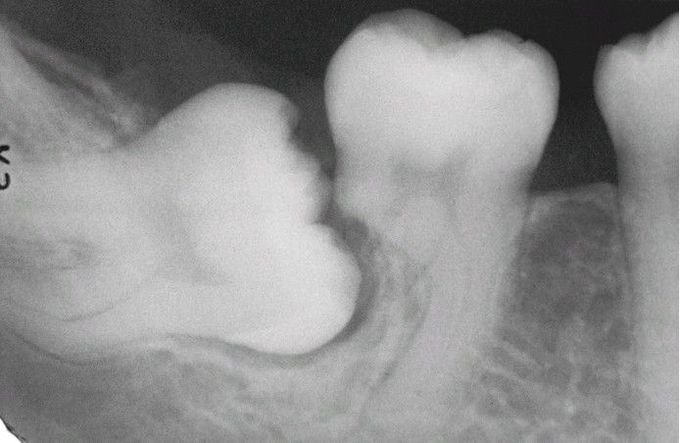

Impaction-Related Tooth Resorption.

Mesioangular impaction of the right mandibular third molar associated with significant resorption of the distal root of the second molar.